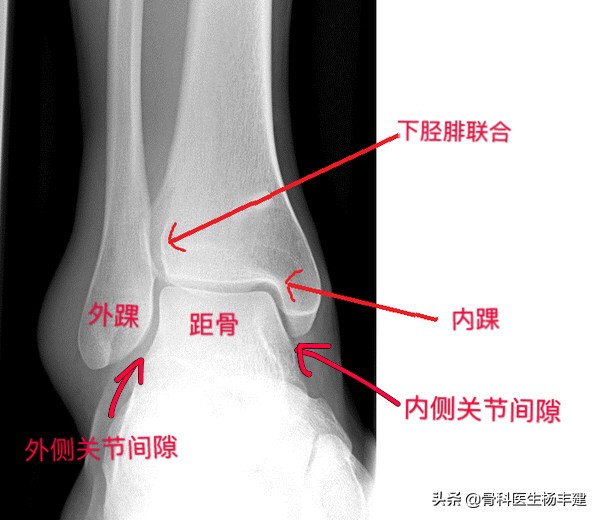

1,为了能够帮助大家理解,需要先解释一下踝关节的解剖。由于我们主要是谈骨折,所以用踝关节正位X光图像作为“模特”。

如图所示,胫骨下端、腓骨下端与距骨一起组成踝关节,其中胫骨下端构成踝关节的顶部和内踝;腓骨下端称为外踝;内踝、外踝以及顶部一起组成一个门形的结构包绕距骨,距骨所在的门形结构称为“踝穴”,距骨两侧的间隙分别称为内侧和外侧关节间隙,通常情况下内侧和外侧的间隙是均匀相等的。

踝关节正位X光图像,可以看到主要的解剖结构

踝穴结构有些类似于自行车的“前叉”,而距骨就好比是自行车的前轮,“前叉”从两侧固定轮子,允许轮子做前后滚动的动作,但是在侧向上要维持稳定。通常来说,距骨不容易发生骨折。我们常说的踝关节骨折,主要是外踝和内踝骨折,有时候会累及“后踝”(胫骨的下端后方,在侧位图像上可以看得比较清楚)。